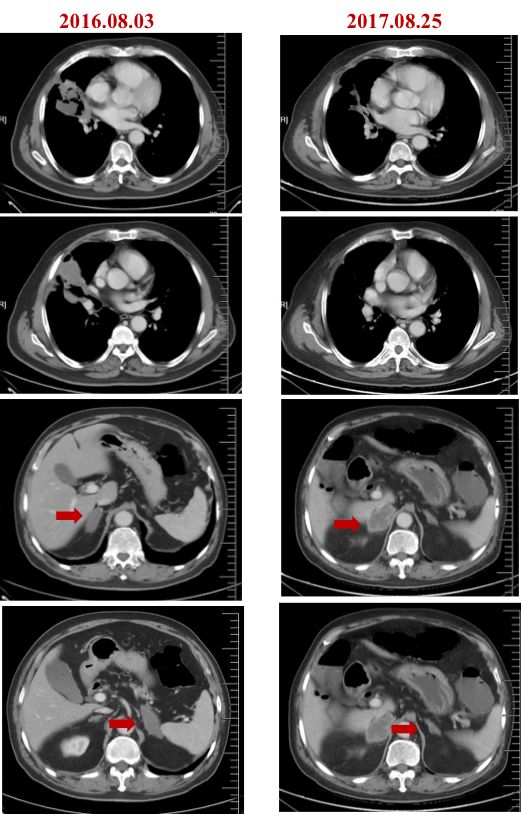

2016年6月,换用吉非替尼(易瑞沙)联合克唑替尼(赛可瑞)治疗,1月后复查,患者肺部和肾上腺病灶明显缩小,疗效PR,直至2017年8月。

(联合治疗前后CT对比)

2017年8月,复查出现右侧肾上腺病灶增大。10月,患者因出现严重低钠血症入院。10月底,影像学显示达到RECIST标准的进展。随后复查血液标本168基因 panel,结果显示:EGFR L858R突变与MET扩增再次出现,L858R突变丰度达3.72%,MET拷贝数2.91。